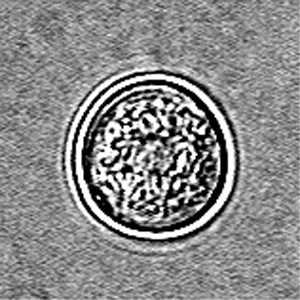

E.histolytica cyst

four nuclei and a chromatoid body with blunt ends